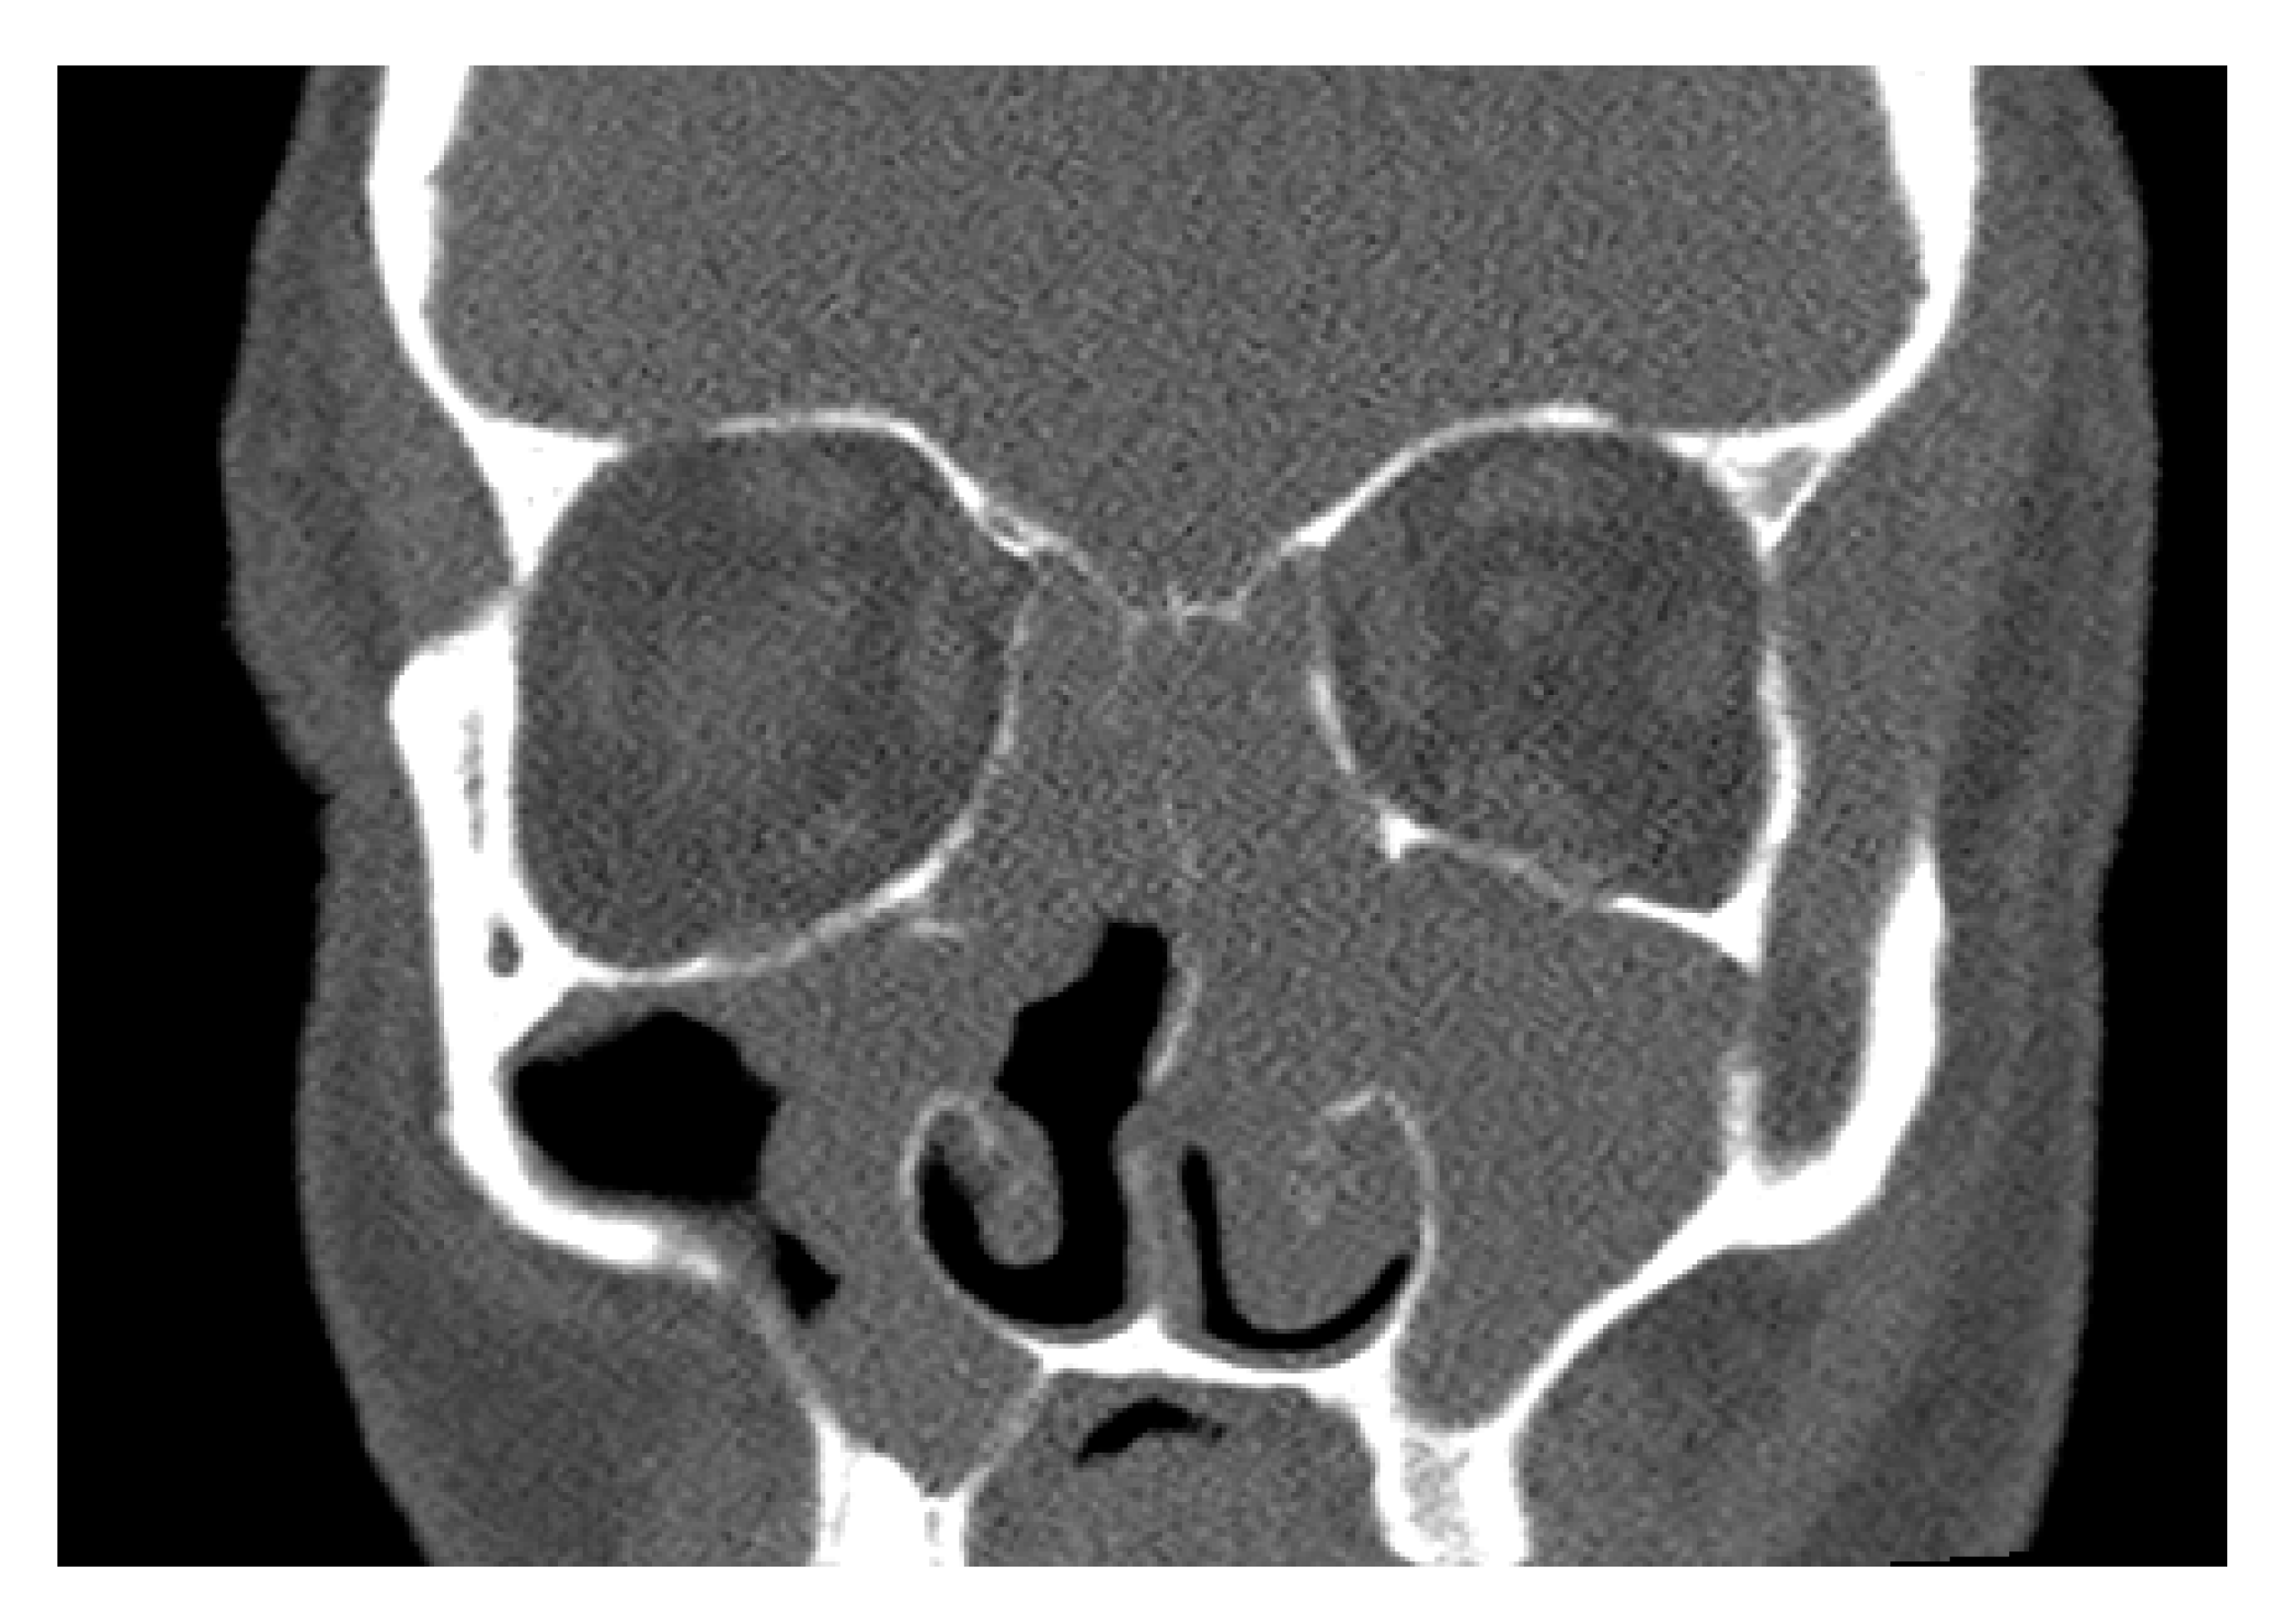

- Kovar, D.; Holy, R.; Voldrich, Z.; Fundova, P.; Astl, J. The Contribution of CT Navigation in Endoscopic Sinus Surgery: An Evaluation of Patient Postoperative Quality of Life and Olfaction Function Results. Otorinolaryngol. Foniatr. 2017, 66, 205–209. [Google Scholar]